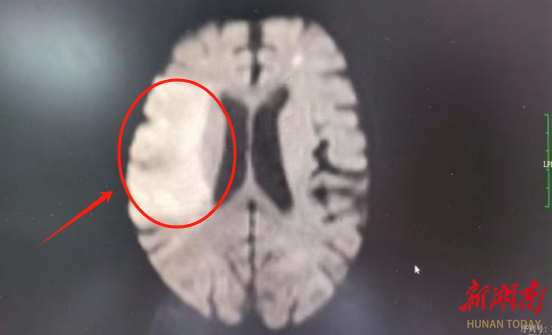

红圈内白色区域为颅内血管堵塞导致的缺血部位

术前检查显示脑部血管严重堵塞,术后脑血管造影则清晰可见血管通畅,生命通道成功重启。